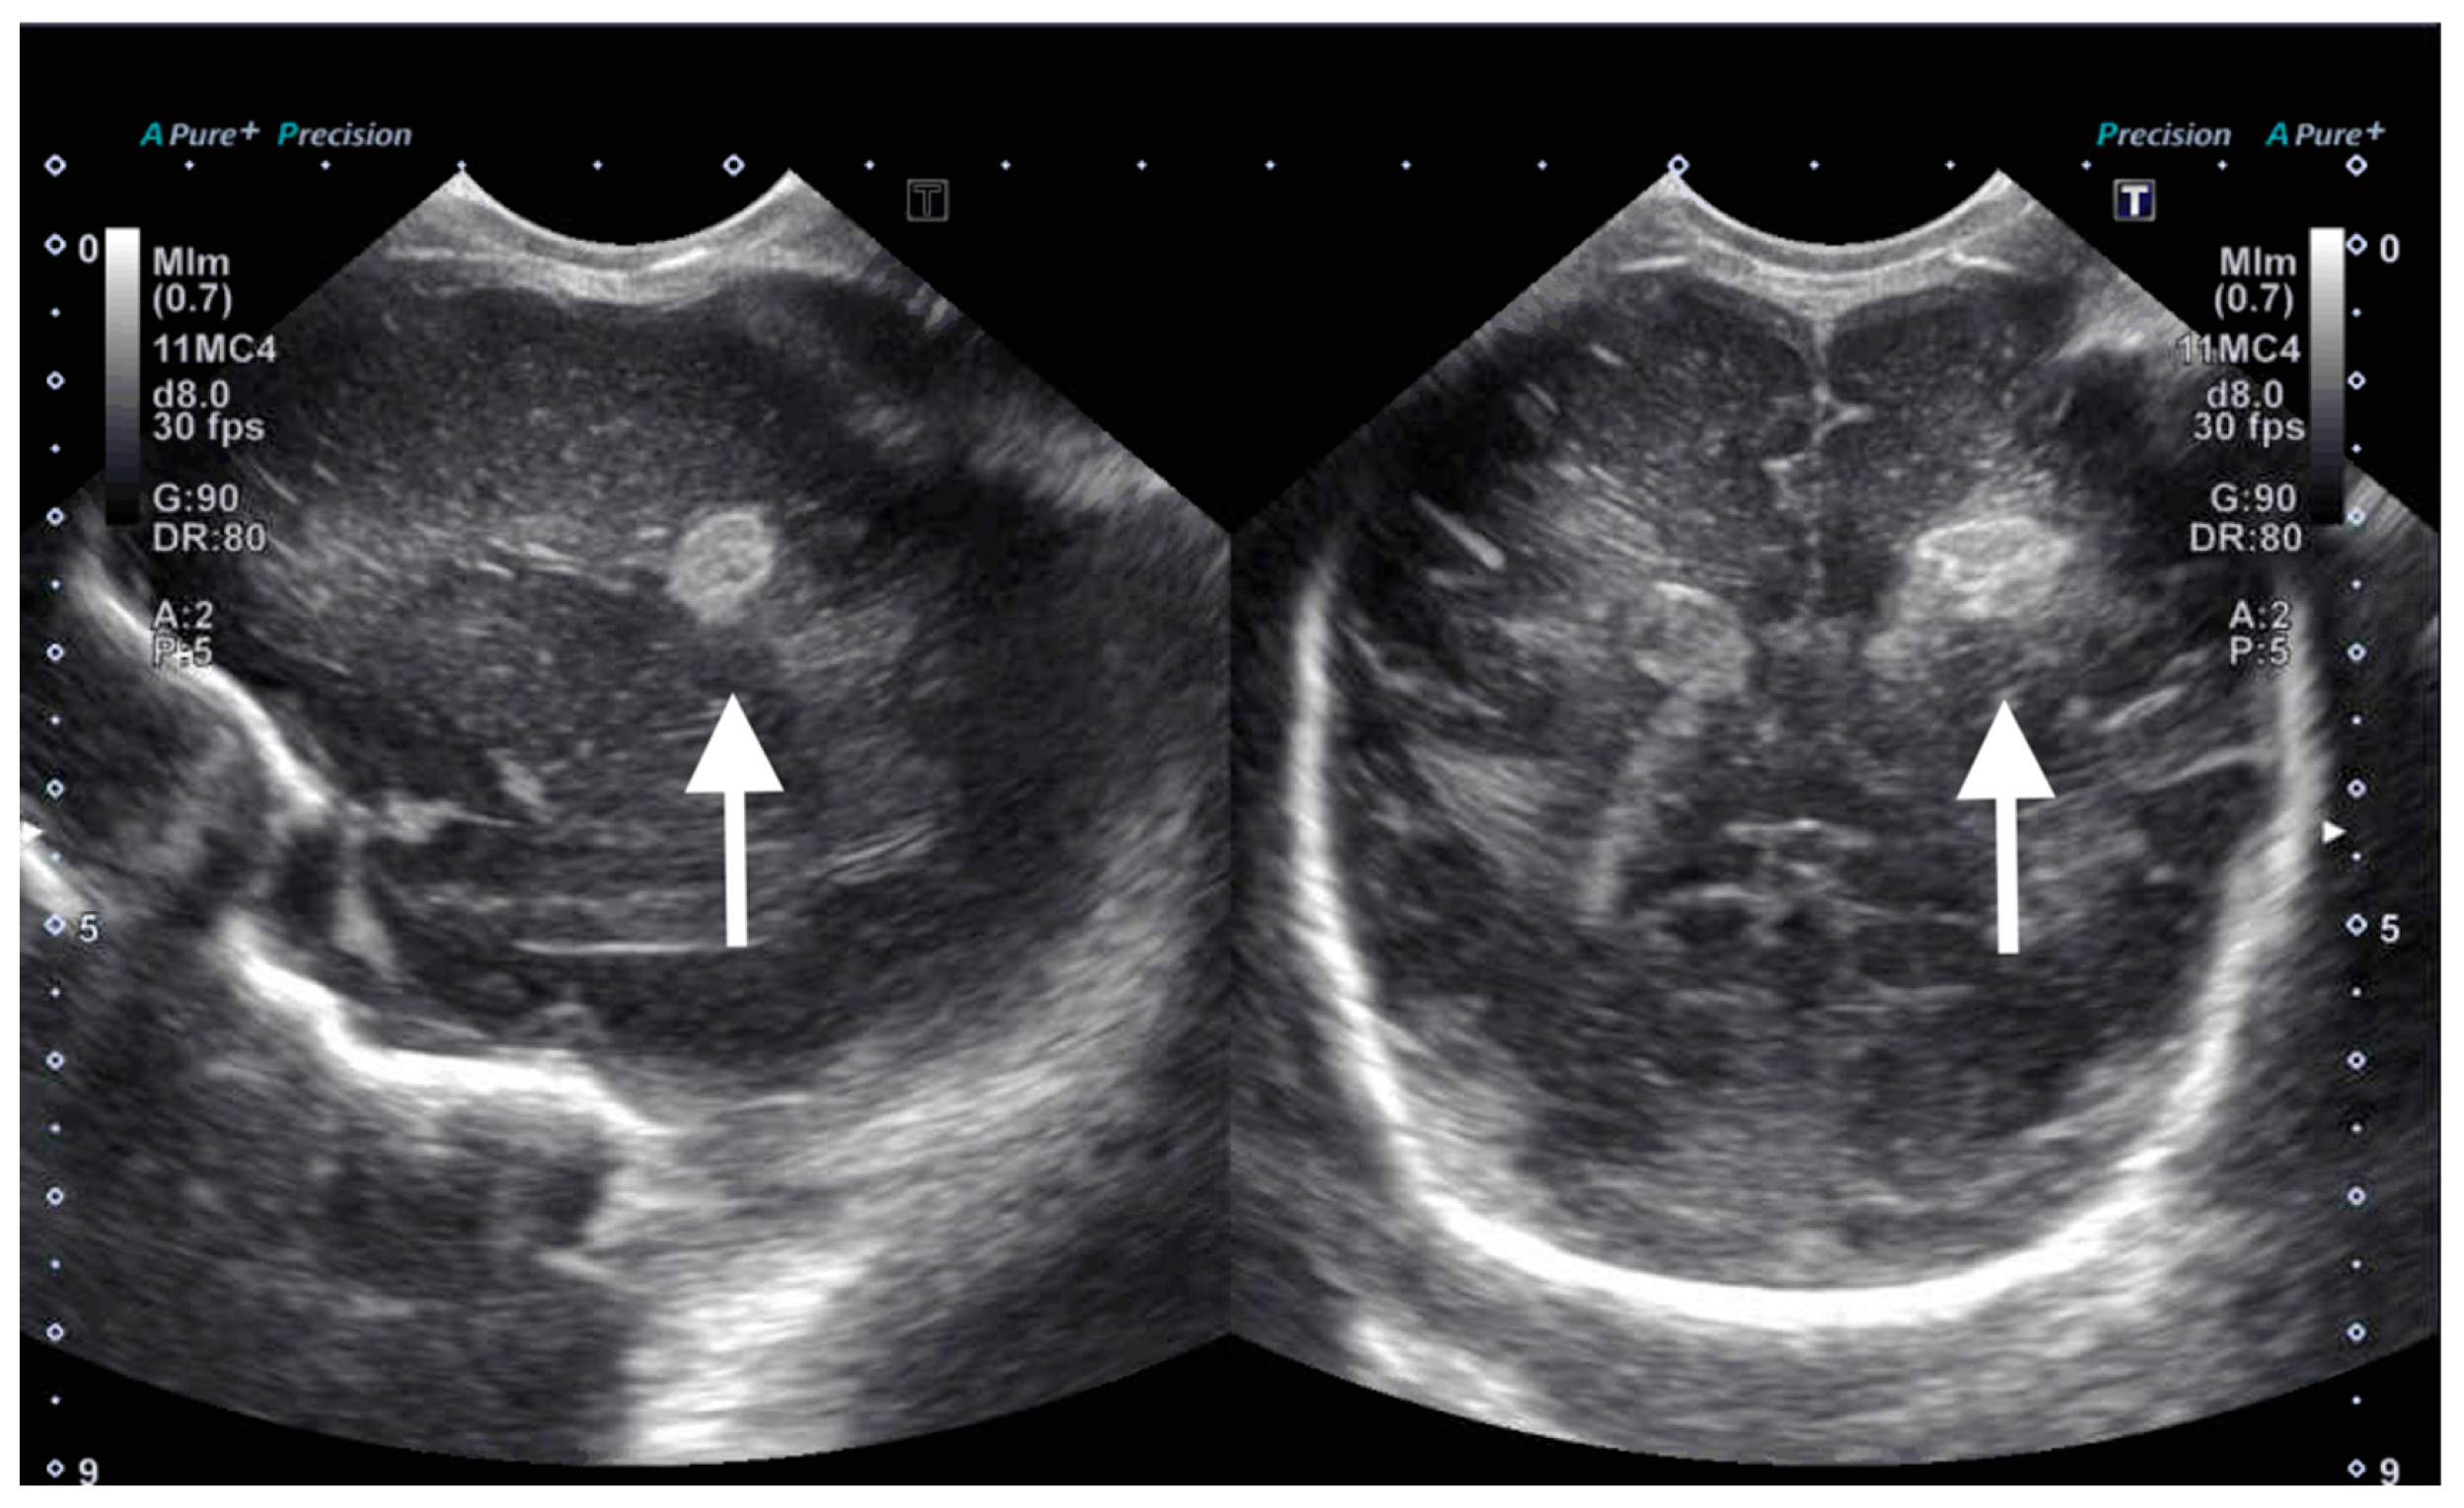

On DOL 5, the patient developed worsening abdominal distention with increased free fluid, rising lactate level, and continued oliguria with minimal brown-colored output, indicating potential bladder rupture. Renal ultrasound at that time demonstrated structurally normal kidneys and ureters, with contusive injuries in the parenchyma (Figure 1 and Figure 2). Pediatric urology was consulted. Diagnostic paracenteses and non-voiding cystogram showed no urinary leak. Computed tomography (CT) of the abdomen and pelvis was performed to further evaluate for free fluid or perforated viscus showed no renal contusion, but noted both kidneys had patchy opacification in the capsule and medulla, consistent with bilateral renal cortical necrosis (Figure 3). Cranial ultrasound was also performed at this time and showed focal parenchymal hemorrhage in the posterior portion of the left frontal lobe (Figure 4).

Figure 1.

Ultrasound of right kidney on day of life 5 showing increased echogenicity (arrow) compared to that of the adjacent liver (asterisk).